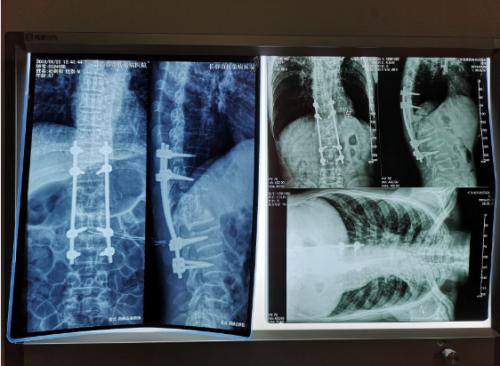

经过检查,罗坚主任凭着丰富的临床经验初步认为王大爷患的是胸椎结核伴脊髓压迫症,那么是什么原因导致的?通过脊柱磁共振检查,罗主任发现王大爷患胸椎脊髓压迫的元凶正是“骨结核”。王大爷胸椎骨7-11节被结核杆菌严重侵蚀,在重体力活后,胸椎脊髓神经受到压迫,最终导致下肢瘫痪。同时患者双肺结核伴左上叶不张,左侧胸腔大量积液。如果等待双肺结核治愈,需时日很长,脊髓的受压如果不能及时解除,导致脊髓变性,那么瘫痪就难以恢复了,在积极治疗肺结核胸腔积液引流,罗坚主任为王大爷尽快安排实施手术。

手术过程中,病人腰大肌脓肿巨大,病椎破坏重游离死骨多,结核物质使脊髓严重受压,既要侧前方减压清除病灶,又要完成后凸畸形的矫正,再由于王大爷年龄较大、体质差,风险高,对技术与手术期管理都是很大的挑战。

罗坚、陈松峰和任重三位医师组成的团队实施手术。罗坚主任凭借其多年外科生涯中大量胸椎结核手术所积累的丰富经验,在脊柱侧前方减压,病灶清除、植骨和后凸畸形矫正胸膜外操作。手术按计划顺利完成,而辗转数家医院的“求医记”终于告一段落,在外等候的家人听到手术成功的消息后喜极而泣。